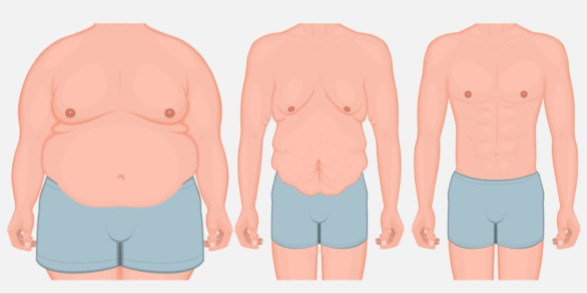

کوچک کردن سینه آقایان یا ژنیکوماتسی

بزرگ بودن سینه در آقایان (ژنیکوماستی) مشکلی است که به دلایل مختلفی بروز می کند، بزرگ بودن سینه علاوه بر تخریب زیبایی ظاهری و اندام ممکن است ایجاد درد و تورم بنماید که منجر به تقاضای شخص به کوچک کردن سینه می گردد. این مشکل که به دلیل رشد غیر طبیعی غدد پستانی در مردان اتفاق می افتد، در بسیاری از موارد منجر به بزرگ شدن بیش از اندازه سینه و در نهایت افتادگی آن می شود، این مشکل به صورت شایع در نوجوانان دیده می شود و ممکن است در نوزادان و یا افراد مسن نیز بروز نماید.ژنیکوماستی که نوعی بیماری یا اختلال متابولیکی می باشد به راحتی توسط جراحی ژنیکوماستی قابل درمان بوده و باعث بهبود ظاهر و کاهش درد و تورمات در بدن فرد می شود